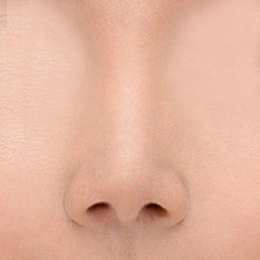

بینی رو به بالا یا بینی کوتاه به بینی ای اطلاق می شود که نسبت به صورت شخص بسیار کوتاه است. و در نمای جلویی دارای سوراخ های بینی بیش از حد قابل مشاهده است. بینی کوتاه یکی از بزرگترین چالش های جراحی زیبایی بینی است. این نوع بدشکلی معمولاً هر 3 لایه بافت بینی (یعنی پوست، پوشش داخلی، حمایت از استخوان) را درگیر می کند. بینی های کوتاه هم مشکلات زیبایی و هم نقص عملکردی دارند. زمانی که رینوپلاستی بینی کوتاه به طور ماهرانه انجام شود، می تواند بهبود چشمگیری ایجاد کند.

بینی کوتاه کلاسیک به سمت بالا و حالت فرورفتگی دارد به طور خاص، به عنوان بینی بدون ابعاد از زاویه نازو فرونتال تا نوک تعریف می شود. فقدان برآمدگی نوک اغلب در تشخیص وجود دارد. برای تعیین اینکه آیا بینی کوتاه وجود دارد، جراح ابتدا باید از ابعاد بینی طبیعی آگاه باشد. هنگام شناسایی بینی کوتاه، تجزیه و تحلیل تمام صورت، به ویژه نیمرخ، همراه با آنالیز به ویژه بینی انجام می شود.

حالت بینی زاویه دار رو به بالا

پوست و بافت های نرم نوک بینی با زاویه رو به بالا برداشته می شوند، سپس نوک بینی بعد از اینکه به سمت پایین کشیده شود ثابت می شود و غضروف اصلاح می شود تا بلند به نظر برسد.

زمانی که طول بینی کوتاه است

اگر طول کلی بینی کوتاه باشد، با استفاده از غضروف خودزا یا اتوژن (autogenous)، طول کلی بینی کشیده می شود.